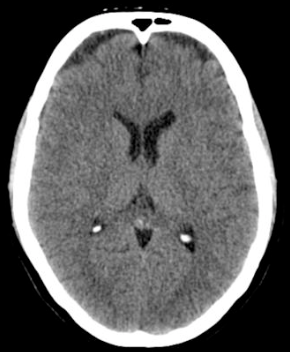

Acute blood shows up brighter on which type of scan. X-ray CT MRI T1 MRI T2 Ultrasound

**CT**

Which vessel is most likely to have ruptured? Left anterior cerebral artery Right anterior cerebral artery Left middle cerebral artery Right middle cerebral artery

The **right middle cerebral artery** is the most likely to have ruptured in this scenario, as this travels out laterally to supply the lateral region of the cortex.

28

What symptoms might the patient experience? [2]

The haemorrhage is in the region of the right middle cerebral artery **Left-sided upper limb paraesthesia** and **left-sided upper limb weakness.** Aphasia is less likely in this case, as Broca’s area (responsible for expressive speech) is most commonly found on the left hemisphere, along with Wernicke’s area (responsible for receptive speech).